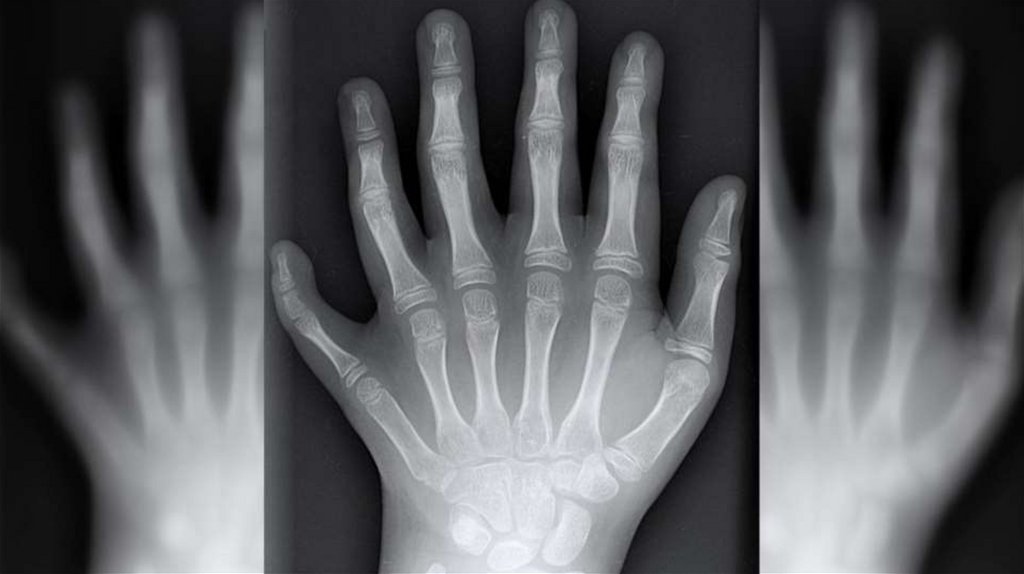

LANGZEITFOLGEN:

GENETISCHE SCHÄDEN

Albinismus

Down Syndrom

Herzfehler

Polydaktylie